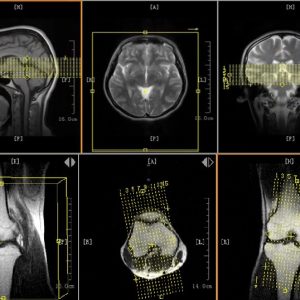

Độ phân giải hình ảnh: Cao, với khả năng tạo ảnh lớp mỏng chi tiết

Gradient mạnh, đáp ứng tốt các chuỗi xung nhanh và mỏng

Cuộn dây RF: Mảng pha đa kênh (4 kênh thu nhận song song)

Tích hợp phần mềm: Tự phát triển, hỗ trợ DICOM, PACS, MIP/MPR 3D

Thu nhận nhanh – chất lượng cao: 4 kênh thu giúp tạo ảnh nhanh và sắc nét

Công nghệ định vị một chạm: 9 lát ảnh scout trong 1 lần chụp giúp lên kế hoạch chụp nhanh chóng

Thần kinh (não, tủy sống, dây thần kinh)

Cơ xương khớp (khớp, chi, cột sống)

Ổ bụng, chậu, niệu – sinh dục

Tim mạch, mạch máu